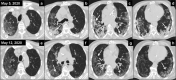

Materials and methods: We conducted a prospective, single-arm, phase 1/2 clinical trial enrolling patients aged ≥50 years, who were coronavirus disease 2019 (COVID-19) positive, at phase 2 or 3 with lung involvement at imaging study and oxygen requirement. Patients received 100 cGy to total lungs in a single fraction. Primary outcome was radiologic response using severity and extension score on baseline computed tomography (CT), at days 3 and 7 after LD-RT. Secondary outcomes were toxicity using Common Terminology Criteria for Adverse Events v.5.0, duration of hospitalization, blood work evolution, and oxygen requirements using SatO2/FiO2 index (SAFI), at days 3 and 7 after LD-RT.

Results: Nine patients were included. Median age was 66 (interquartile range, 57-77). Severity score was stable or decreased in the third CT but was not statistically significant (P = .28); however, there were statistically significant changes in the extension score (P = .03). SAFI index significantly improved 72 hours and 1 week after LD-RT (P = .01). Inflammatory blood parameters decreased 1 week after RT compared with baseline; only lactate dehydrogenase decreased significantly (P = .04). Two patients presented grade 2 lymphopenia after RT and another (with baseline grade 3) worsened to grade 4. Overall, the median number of days of hospitalization was 59 (range, 26-151). After RT the median number of days in the hospital was 13 (range, 4-77). With a median follow-up after RT of 112 days (range, 105-150), 7 patients were discharged and 2 patients died, 1 due to sepsis and the other with severe baseline chronic obstructive pulmonary disease from COVID-19 pneumonia.